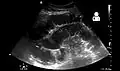

Small bowel obstruction on ultrasound[19]

-

Radiological signs of bowel obstruction include bowel distension (small bowel loops dilated >3 cm) and the presence of multiple (more than 2) air-fluid levels on supine and erect abdominal radiographs.[16] Ultrasounds may be as useful as CT scanning to make the diagnosis.[17]